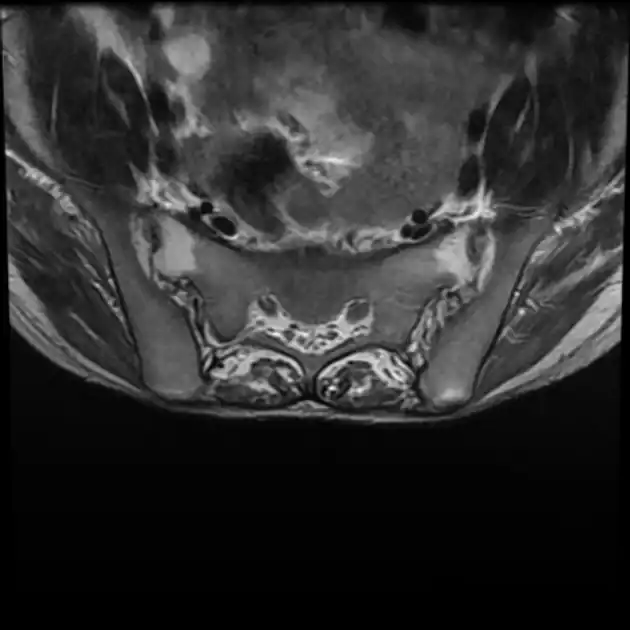

Imaging

X-rays

The earliest changes demonstrable by plain x–ray shows erosions and sclerosis in sacroiliac joints. Progression of the erosions leads to widening of the joint space and bony sclerosis. X-ray spine can reveal squaring of vertebrae with bony spur formation called syndesmophyte. This causes the bamboo spine appearance. A drawback of X-ray diagnosis is the signs and symptoms of AS have usually been established as long as 7–10 years prior to X-ray-evident changes occurring on a plain film X-ray, which means a delay of as long as 10 years before adequate therapies can be introduced.[21]

Options for earlier diagnosis are tomography and MRI of the sacroiliac joints, but the reliability of these tests is still unclear.

T1-weighted MRI with fat suppression after administration of gadolinium contrast showing sacroiliitis in a person with ankylosing spondylitis -